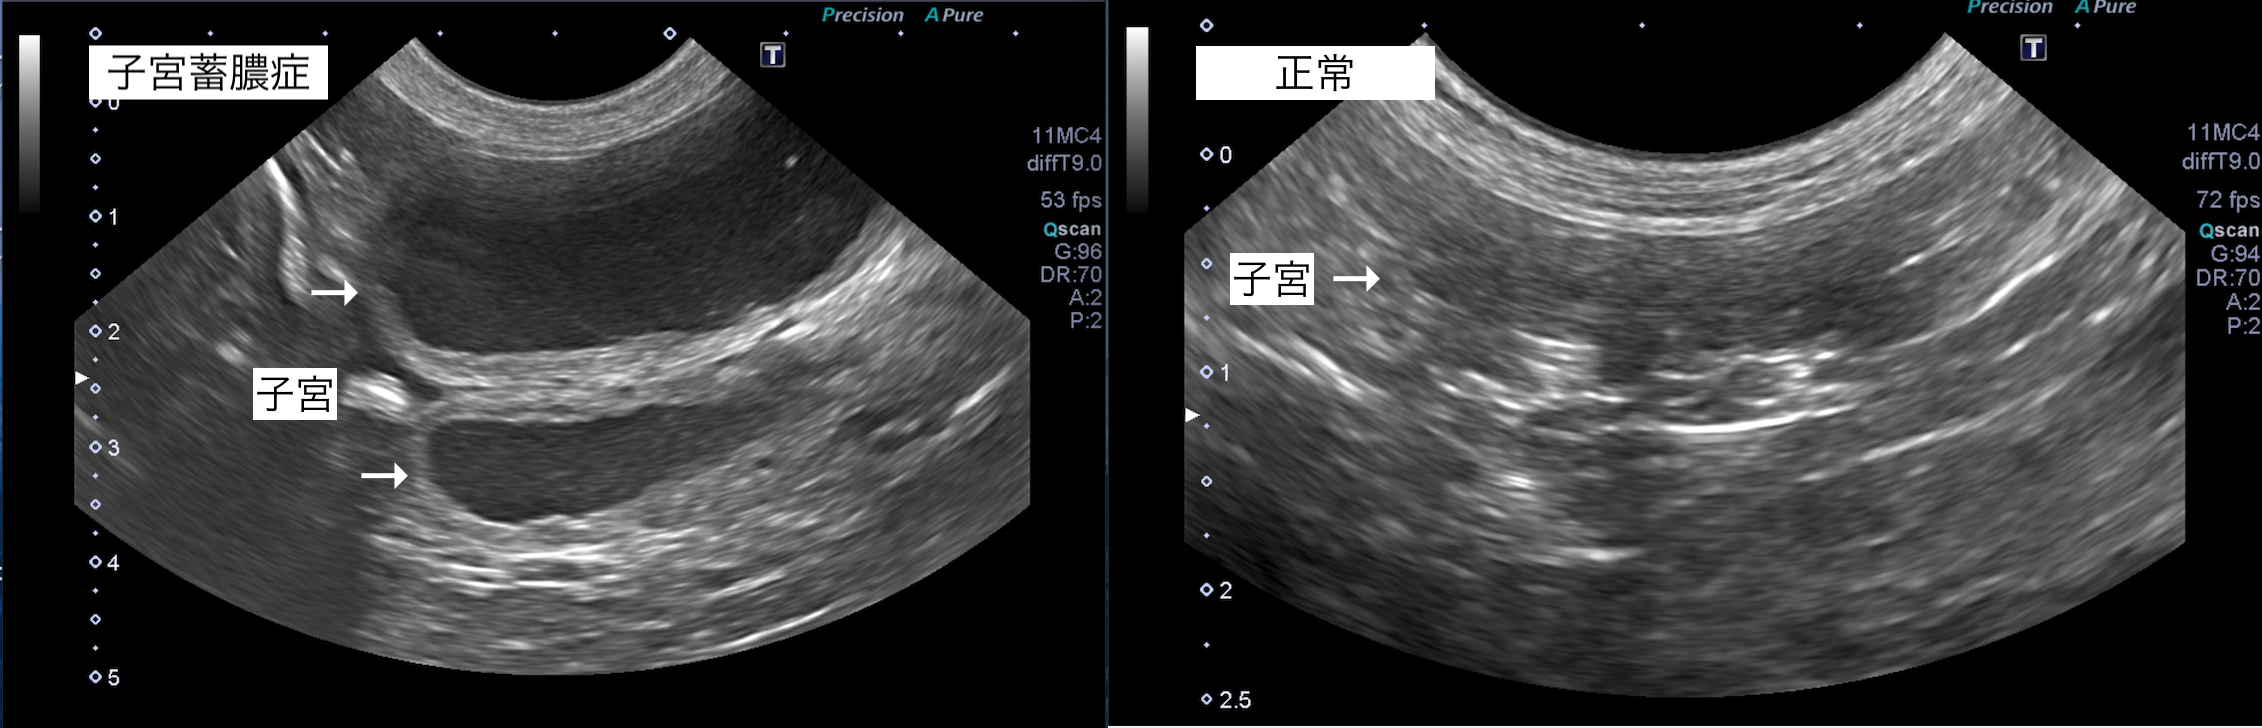

超音波検査では子宮に液体貯留が認められたため、子宮蓄膿症と診断しました。

子宮蓄膿症の犬の1例(避妊・去勢手術)

子宮蓄膿症は、避妊手術を行っていない犬猫に起こり、子宮腔内に膿が溜まってしまう病気です。